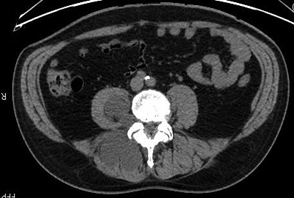

In January 2020, a pelvis CT study of the lumbosacral region revealed multiple hypodense paravertebral formations, referable to joint cysts (Figures 1 & 2). F18G-PET showed a hypermetabolic area (SUV max 3.0) on the right paravertebral muscles at L5-S1 level deepening into the right psoas major muscle.

Figure 2: Axial CT scan.